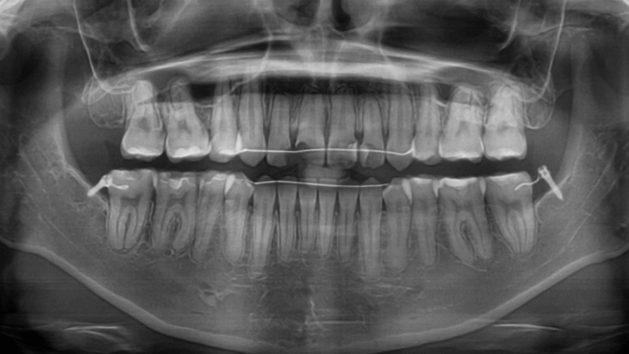

咬み合わせが逆であること(反対咬合)が気になる

| 年齢・性別 | 15歳 女性 |

|---|---|

| 主訴 | 咬み合わせが逆であること(反対咬合)を気にされて来院された女性。見た目や機能面の改善を希望されていました。 |

| 治療期間・回数 | 4年4ヶ月・28回 |

| 費用 | 900,000円 |